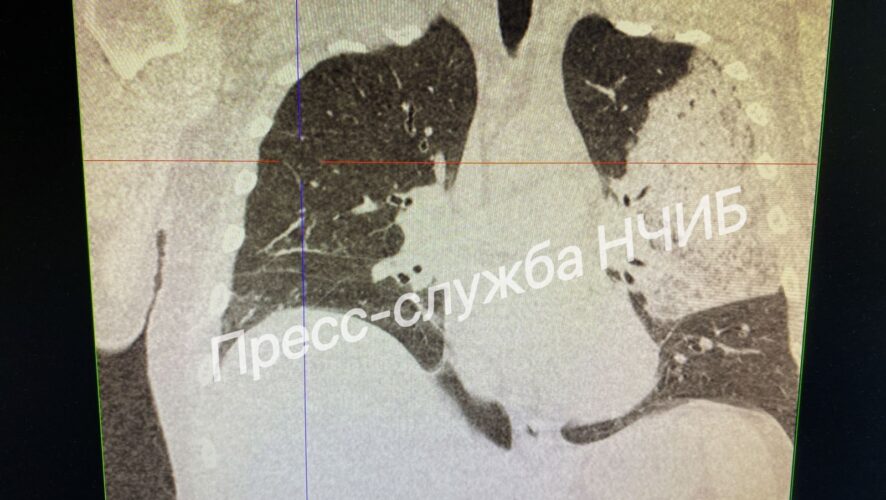

Фото: НЧИБ

По данным специалистов, 51-летний мужчина поступил в больницу с высокой температурой и изнуряющим кашлем. Компьютерная томография выявила обширное поражение легочной ткани. Это потребовало немедленной госпитализации в реанимацию.